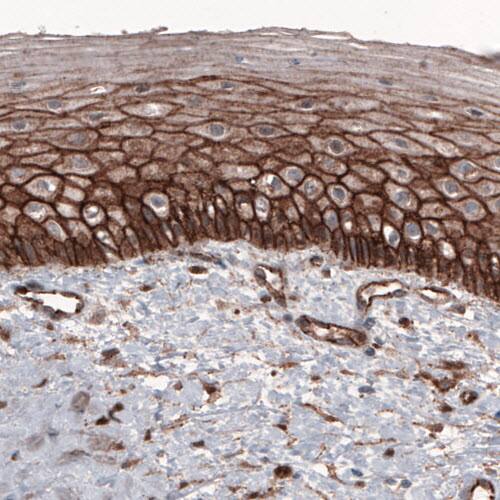

Staining of human cervix shows strong membranous positivity in epithelial cells.